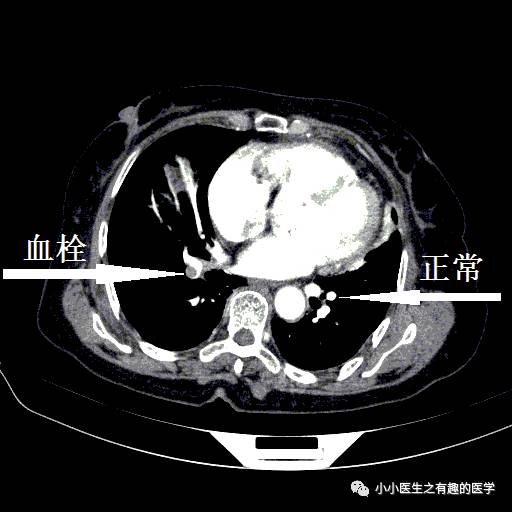

小血栓。

右边也有血栓。